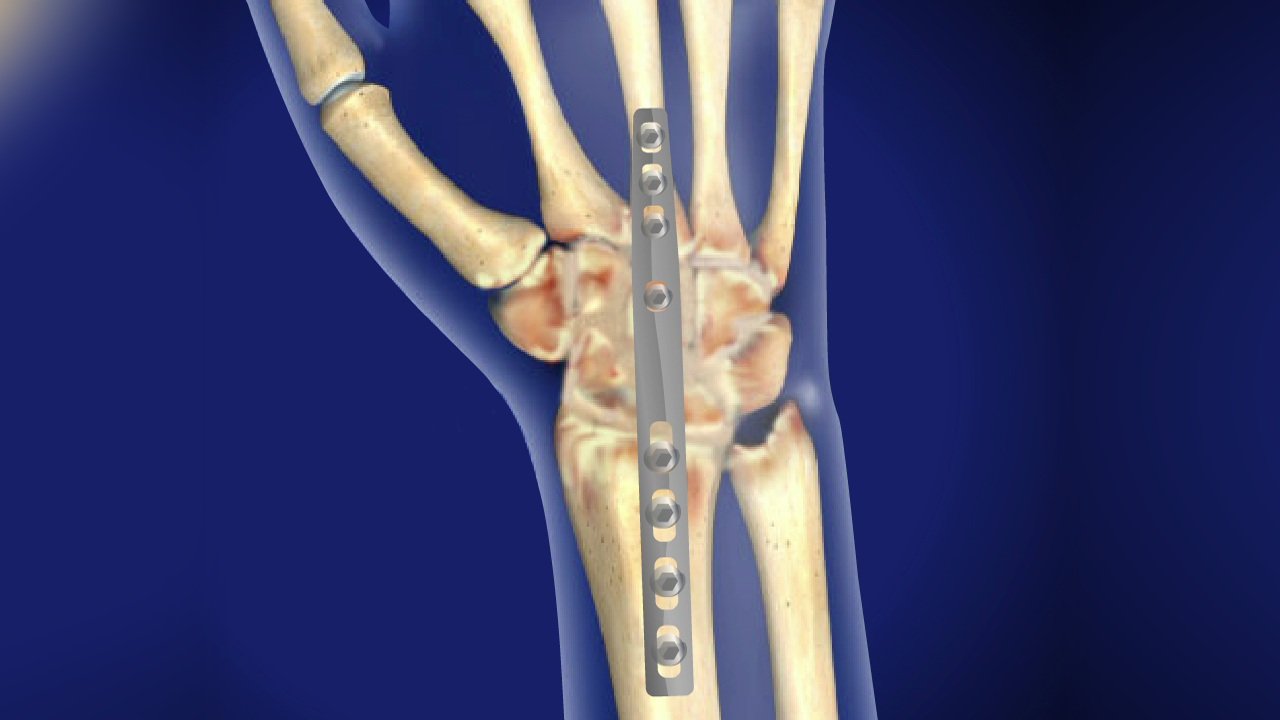

Arthrodesis of wrist joint

Arthrodesis of wrist

It may be defined as surgical fusion of the radiocarpal joint.